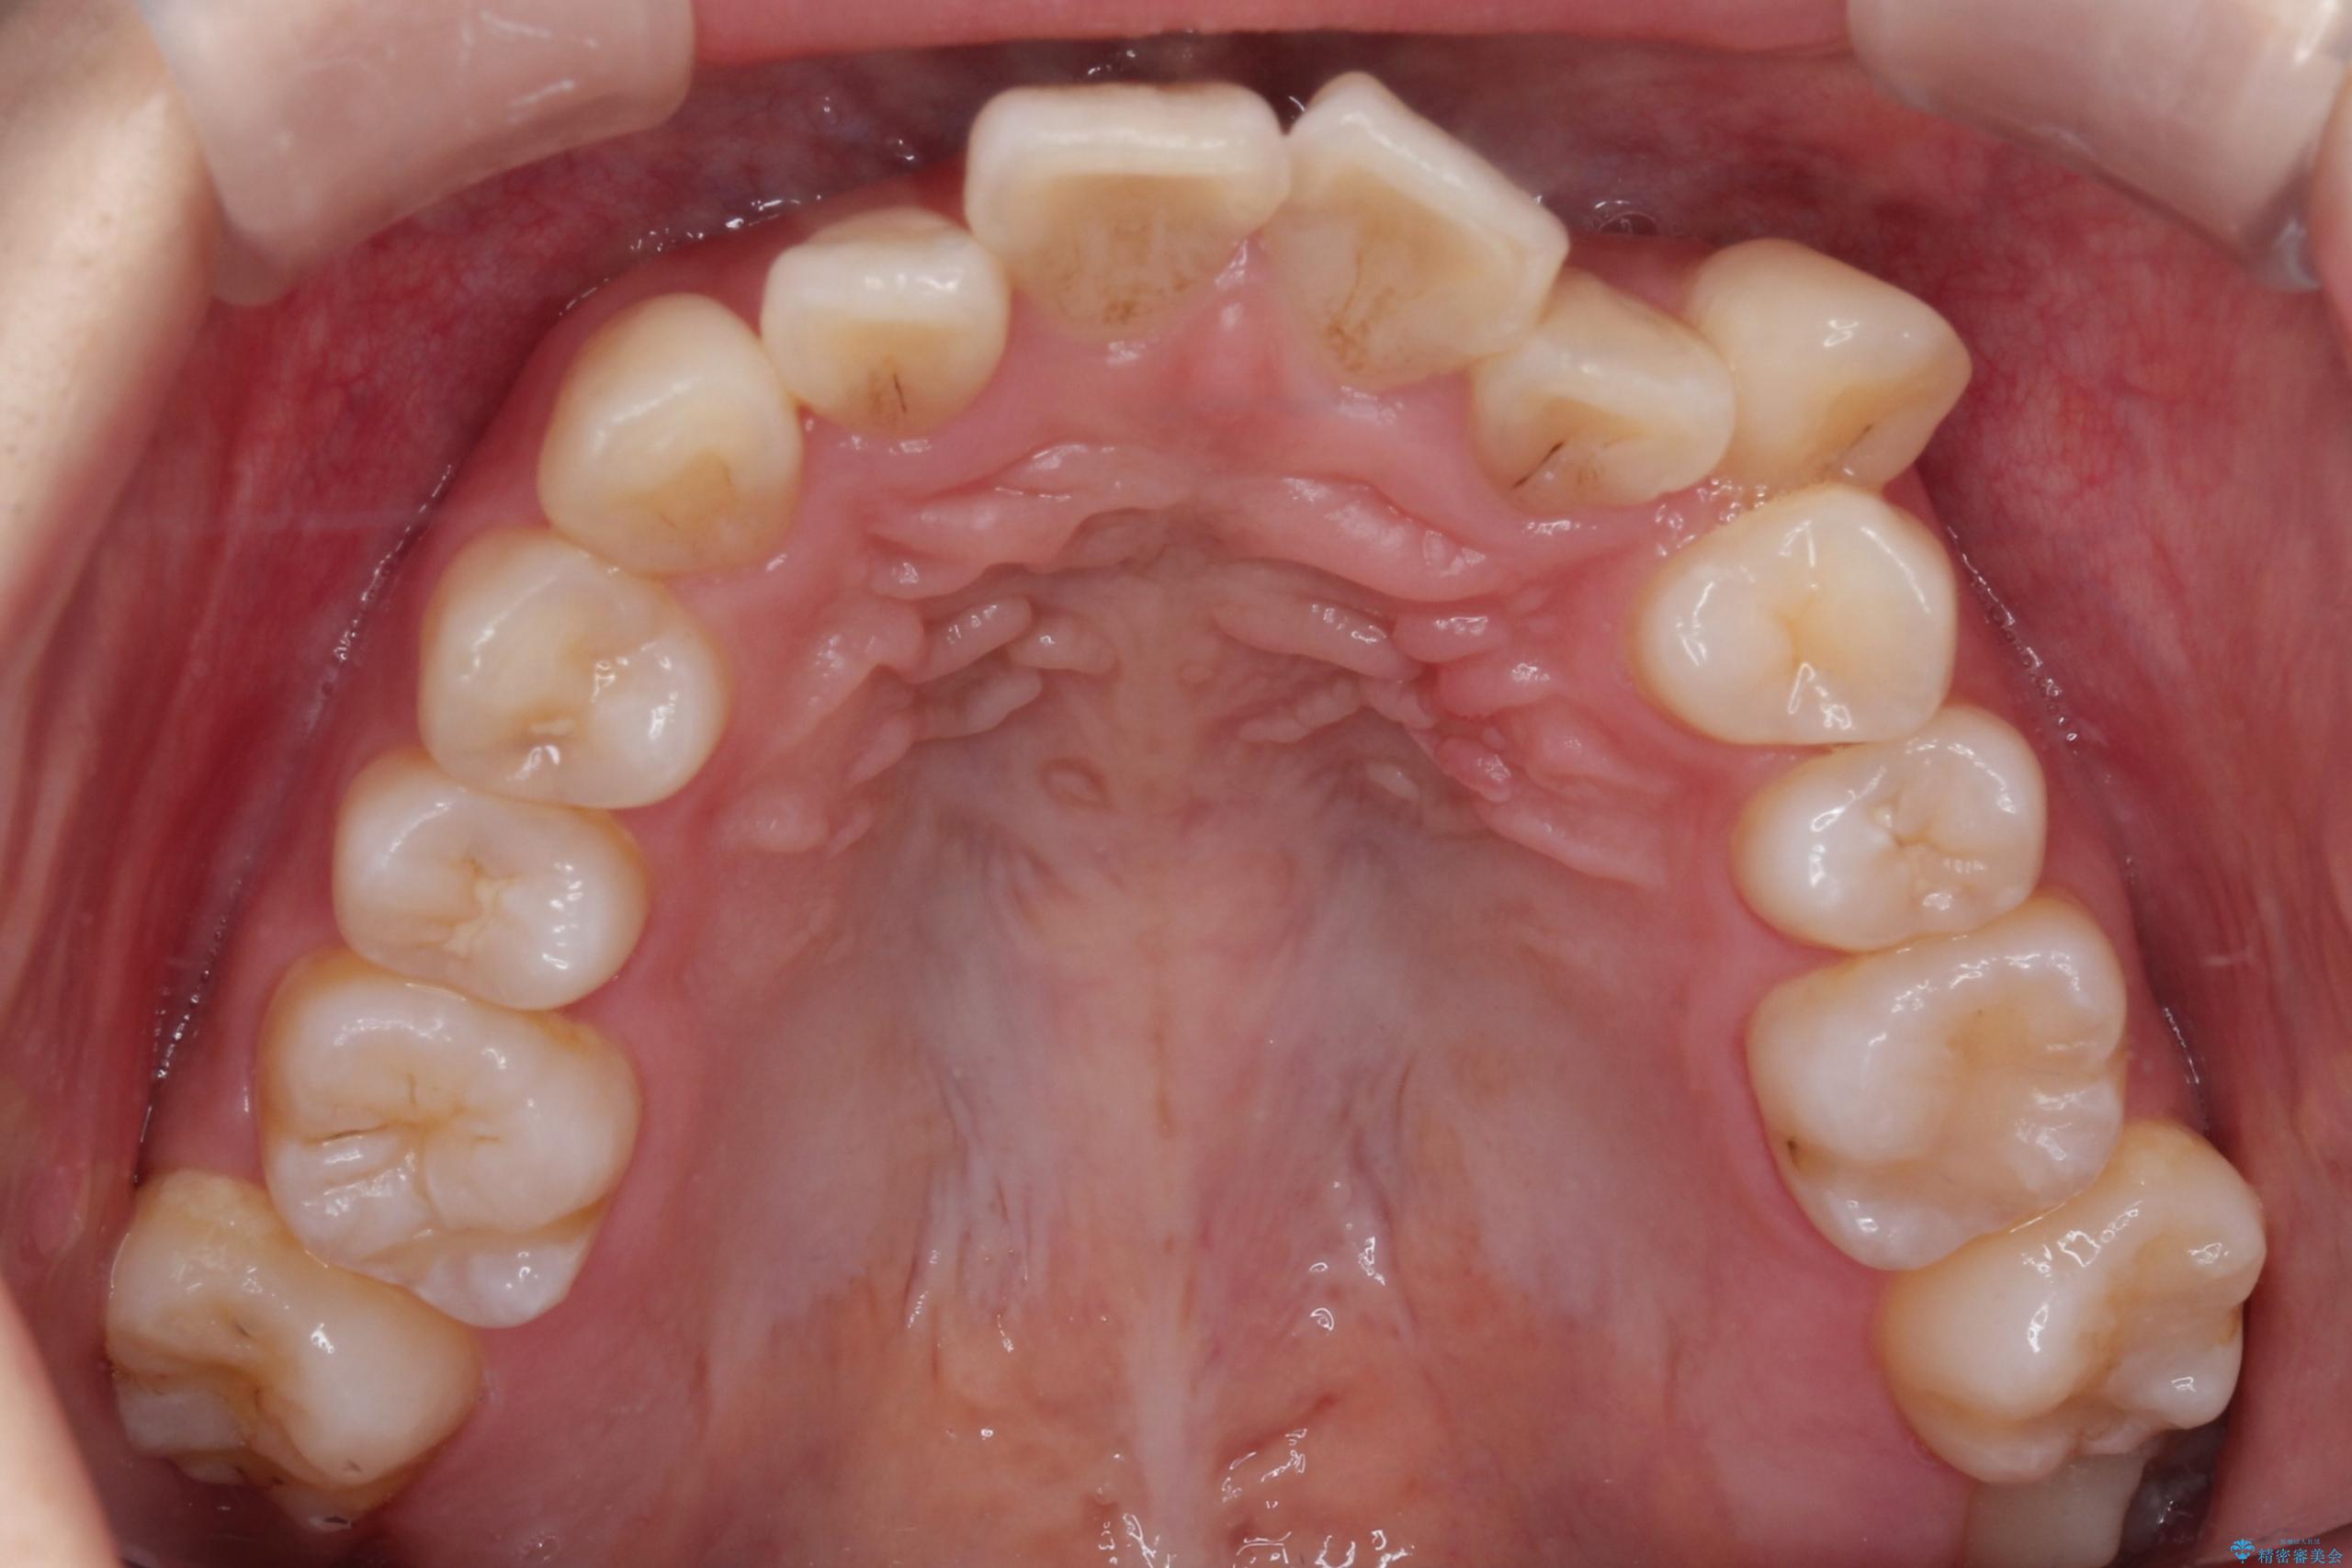

- 八重歯(叢生)と、上下の歯の中心線(正中)がずれていることを主訴にご来院されました。精密な検査の結果、歯列全体のスペースが大幅に不足しており、八重歯を正しい位置に配列し、正中のズレを改善するためには、上下左右の第一小臼歯を抜歯する必要があると診断。装置には、目立ちにくい審美ワイヤーを使用し、見た目を気にせず、機能性と審美性が完璧に整った咬み合わせを目指す治療計画を立案しました。

今回の矯正治療では、まず計画通り上下左右の小臼歯4本を抜歯し、八重歯や正中のズレを解消するための十分なスペースを確保しました。装置には、目立ちにくい白いブラケットとワイヤーを使用した審美ワイヤー矯正を採用。

八重歯: 突出していた八重歯を歯列内に誘導し、デコボコを解消しました。